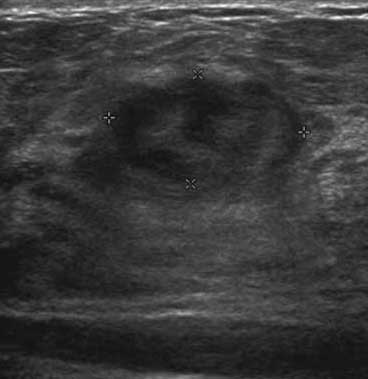

The target dataset was developed from 35 breast ultrasound scans that were segmented by an image-processing expert with extensive experience in breast lesion segmentation (the second author). The images, collected from the Web, are of different dimensions, ranging from to pixels (Figure 3, images resized for sake of illustration). These are the same images used to introduce EFIS originally [1].

Ultrasound images are generally difficult to segment, primarily due to the presence of speckle noise and low level of local contrast. It should be noted that the segmentation of ultrasound actually does require a complete processing chain, (including proper preprocessing and post-processing steps). However, the purpose of using these images was solely to demonstrate that the accuracy of the segmentation can be increased with the application of SC-EFIS.